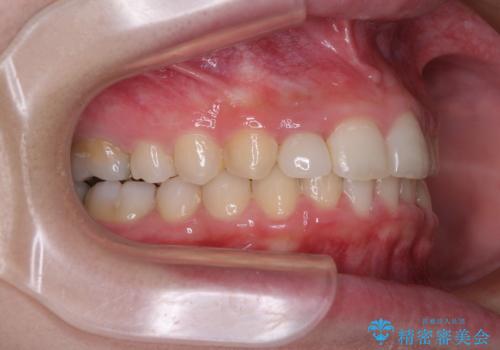

- 前歯の歯並びと不自然な色をした前歯のクラウンを気にして来院された患者様です。

上下前歯の歯列不正はインビザラインにより歯列を整え、その後に、前歯をオーダーメイドタイプのオールセラミッククラウンにて補綴治療することとしました。

前歯のデコボコを一番気にしていらっしゃいましたが、矯正治療により下顎前歯が隠れるほどのディープバイトも一緒に改善され、奥歯に負担のかかりにくい咬み合わせとなりました。